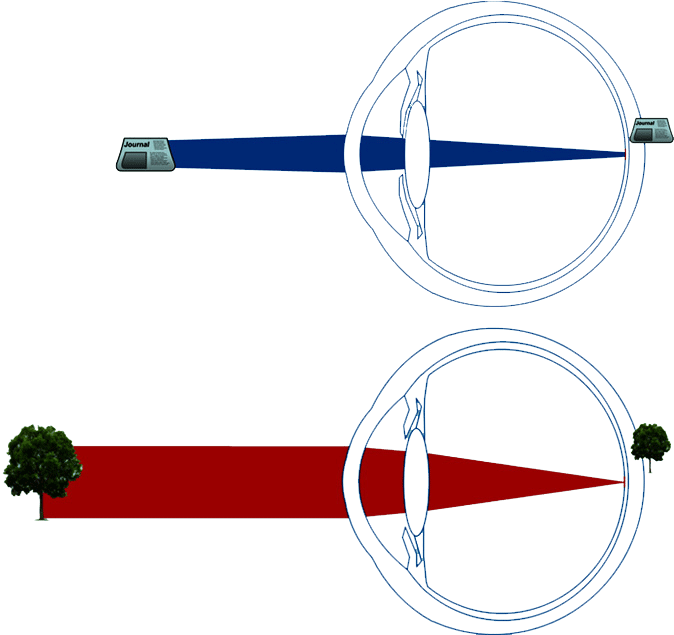

En effet, si l'oeil était statique, l'emmétrope (c'est-à-dire une personne sans défaut de vision) ne pourrait voir net que de loin car les images des objets proches se formeraient en arrière de la rétine et apparaîtraient donc floues.

En augmentant sa puissance, le cristallin permet de corriger cela en ramenant l'image de l'objet sur la rétine.